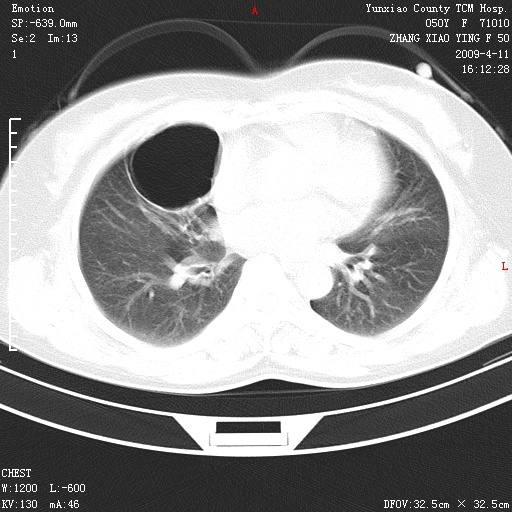

标题: CT19324:胸闷1周伴咳嗽 [打印本页]

标题: CT19324:胸闷1周伴咳嗽

肺囊肿并感染。

胸膜下肺大泡

病灶周围肺纹受压移位走行较柔和,余肺里实质均匀,纹理如常,肺间质无显著纤维化,支持考虑孤立性肺囊肿

考虑右肺中叶肺囊肿。